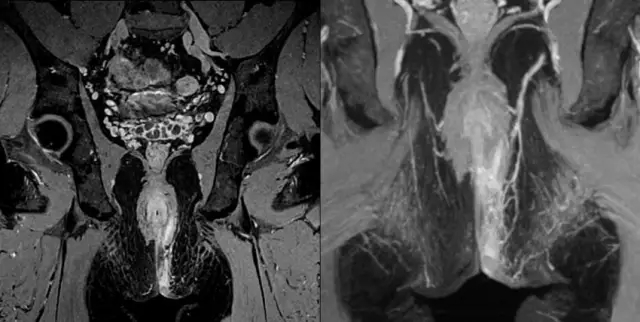

中醫(yī)骨傷科的診斷對磁場均勻性提出極高要求。聯(lián)影中醫(yī)磁共振搭載業(yè)界最佳均勻度磁體,確保大視野邊緣圖像質(zhì)量;針對各關(guān)節(jié)開發(fā)專用線圈,以特殊設(shè)計(jì)線圈結(jié)構(gòu)及更高線圈單元密度,實(shí)現(xiàn)各關(guān)節(jié)高清快速成像;搭載增強(qiáng)延遲軟骨成像技術(shù),提前發(fā)現(xiàn)軟骨細(xì)微變化,對骨傷科疾病的早期探查、精確診斷和愈后評估均有重要臨床意義。

聯(lián)影醫(yī)療發(fā)布業(yè)界首臺中醫(yī)磁共振成像系統(tǒng)

使用聯(lián)影關(guān)節(jié)專用線圈獲取的髖關(guān)節(jié)、膝關(guān)節(jié)、踝關(guān)節(jié)、肩關(guān)節(jié)、肘關(guān)節(jié)、腕關(guān)節(jié)圖像